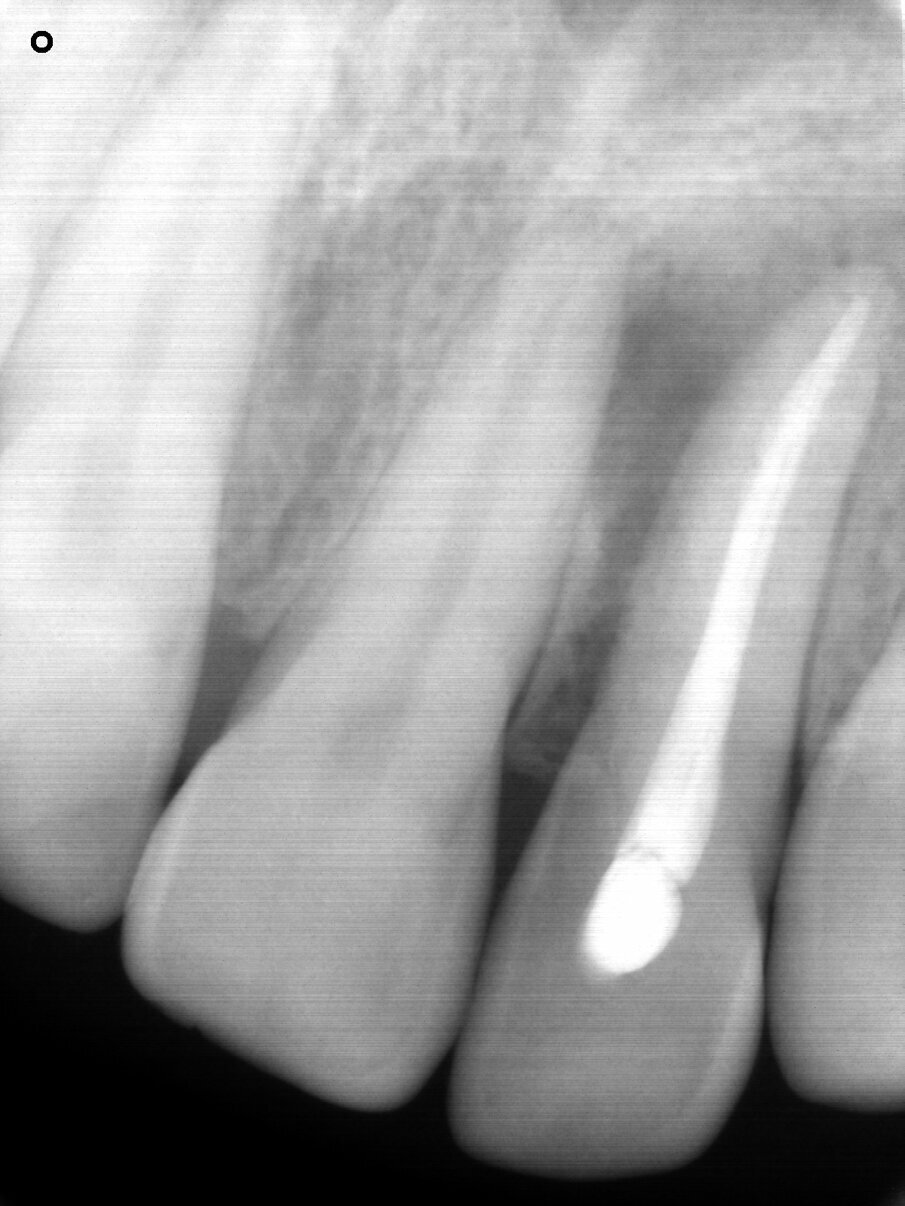

A 48-year-old male patient presented with a horizontal fracture of tooth #22 (Fig. 1). He complained of swelling of the tooth’s periapical area, and the periapical radiograph revealed a horizontal fracture with an unfavourable root–crown ratio (Fig. 2).

Fig. 2: Periapical radiograph showing the horizontal fracture of the endodontically treated tooth #22 and an unfavourable root–crown ratio.